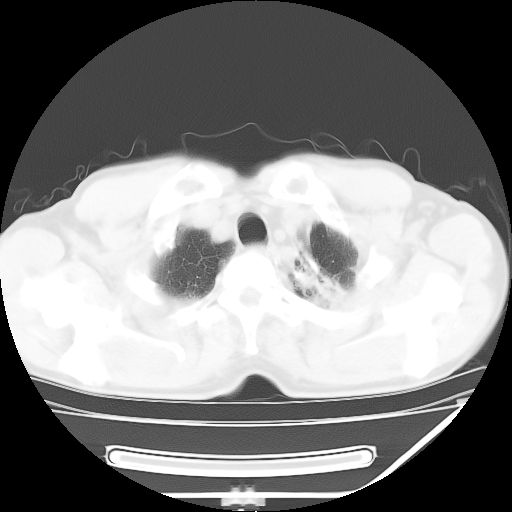

男,59岁,“结核性胸膜炎”30余年,胸部经常疼痛,多次x检查提示“肺部”炎症。腹部疼痛5日,b超提示:“肝内短管结石,余显示不清,建议进一步检查。”

两肺结核并右侧胸腔积液;脾脏、腹腔及腹膜后淋巴结结核[陈旧性];肝内胆管结石

胸部腹部都是结核(双肺。纵隔淋巴结,肝脏,脾脏,肠系膜)

两肺结核并右侧胸腔积液;脾脏、腹腔及腹膜后淋巴结结核[陈旧性];肝内胆管结石。直肠息肉?